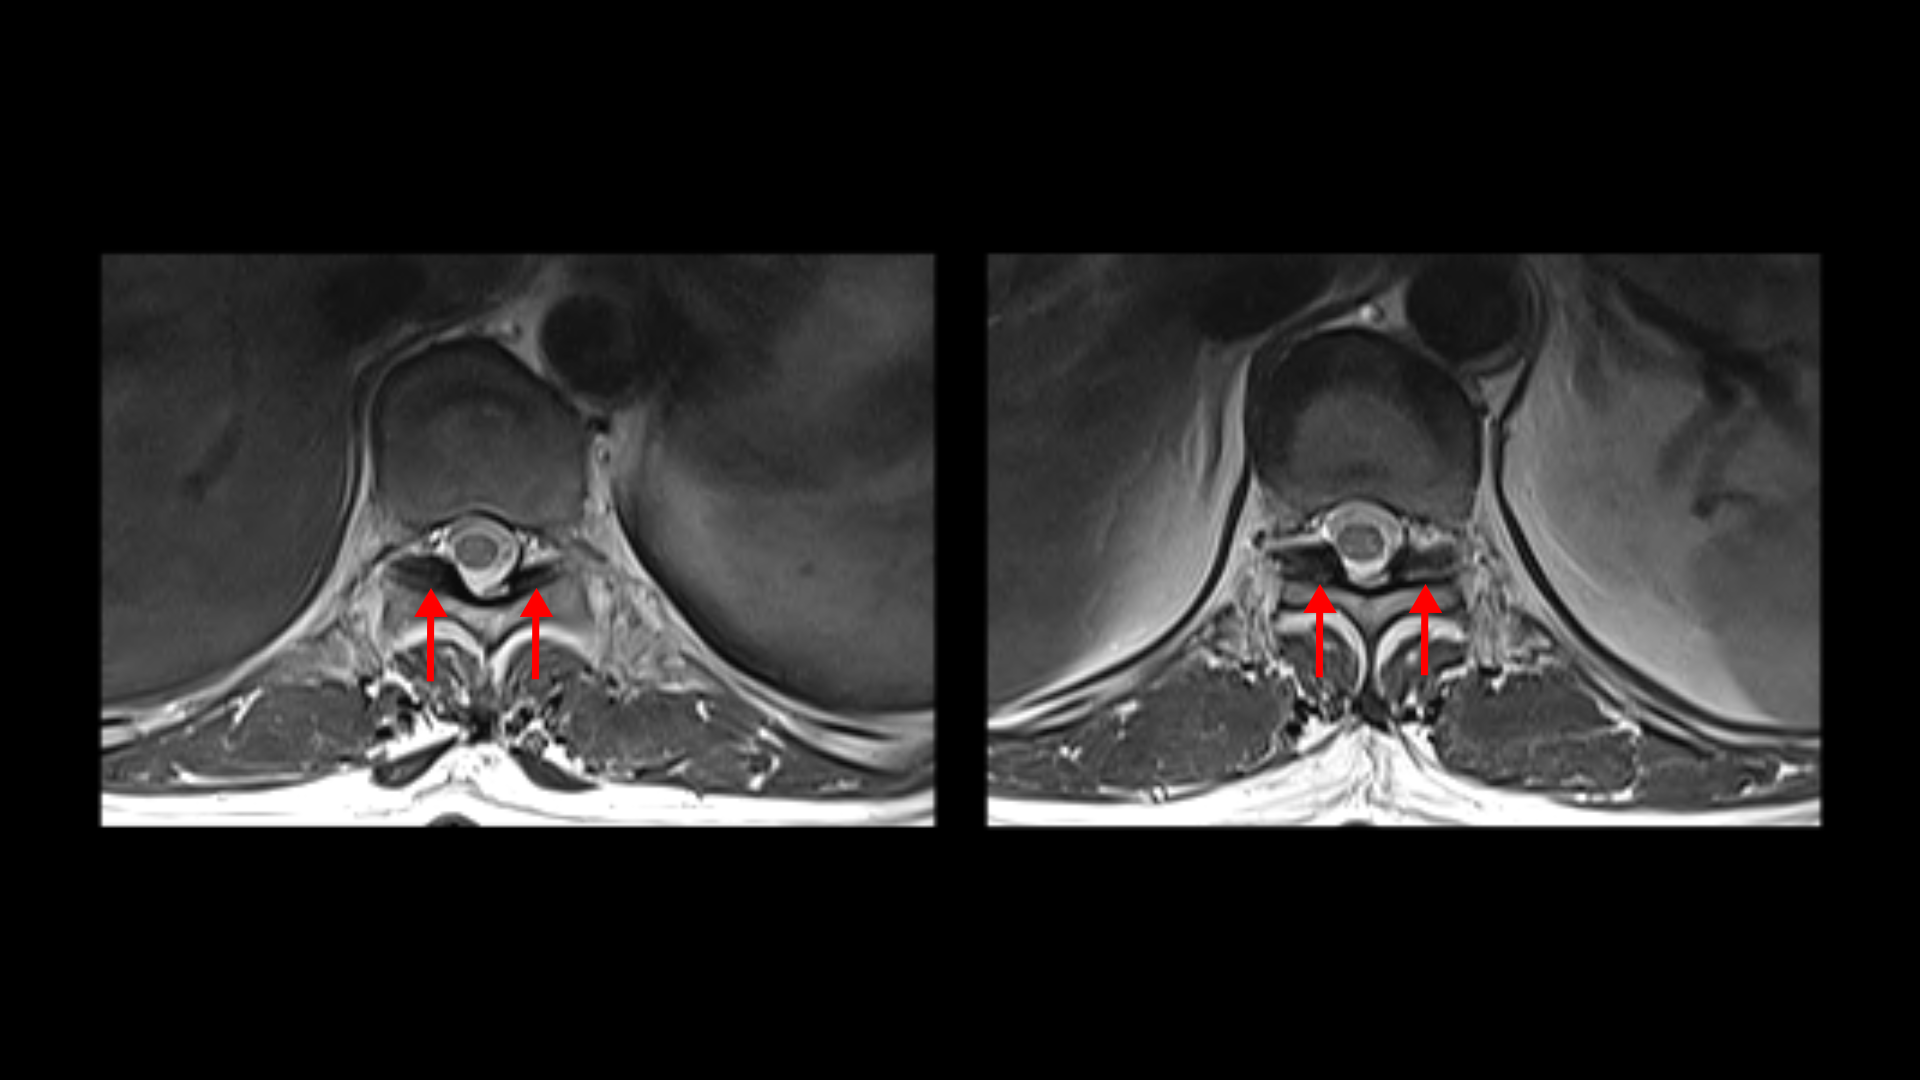

우선 이 환자분의 X-ray를 보면 5번 1번에 전방전위증으로 인한 불안정성이 있습니다. 척추가 불안정하므로 전방전위로 뼈가 밀려 나간 정도가 MRI에 보이는 것보다 X-ray 굴곡상태에서 보는 게 훨씬 더 심해 보입니다. 또 척추 여러 마디에 퇴행성 병변이 보입니다.

먼저 5번 1번에 척추관 내의 황색인대의 골화 현상이 보이고

후관절의 퇴행도 심해 보입니다.

그리고 허리 4마디에 퇴행성 허리디스크가 있습니다.